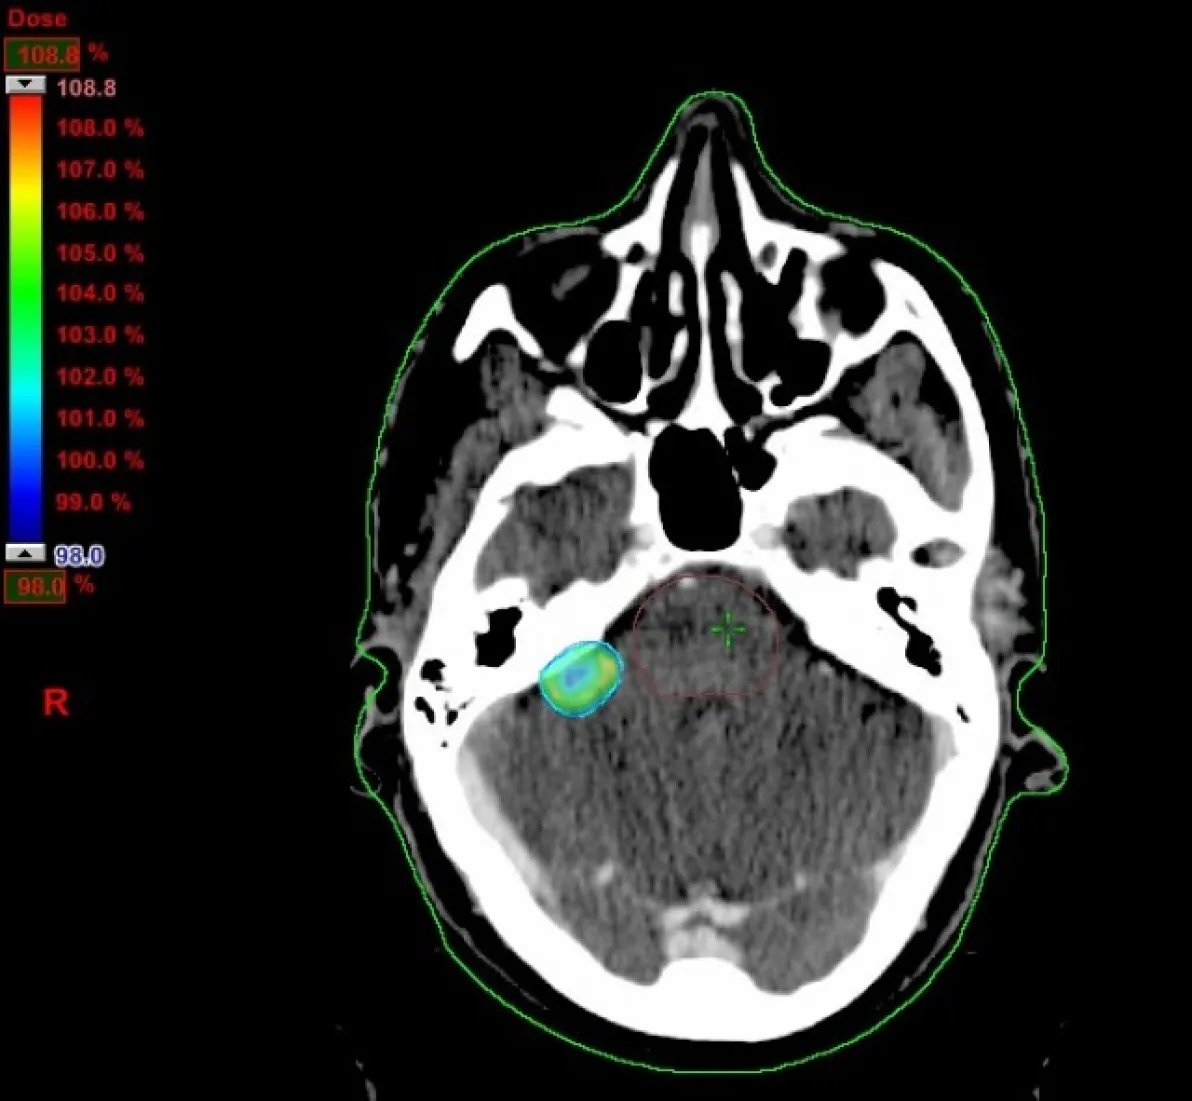

En Jahr nach der Umsetzung der fraktionierten stereotaktischen Strahlentherapie ist die Abteilung für Radioonkologie im Krankenhaus IMED Elche noch einen Schritt  weitergegangen und wird das erste medizinische Zentrum der Provinz Alicante, dass für eine Radiochirurgie die volumetrischen Therapietechnik RapidArc (Varian) anwendet.

Die Radiochirurgie ist eine stereotaktische Strahlentherapie im Bereich des Gehirnschädels, die bei Tumoren, kleiner als 3cm, angewandt wird. Sie wird in einzelnen Sitzungen mit sehr hohen Dosen durchgeführt und das Behandlungsvolumen setzt höchste Präzision voraus. Das Verfahren erfordert eine perfekte Koordination aller beteiligten Mitarbeiter (Radiologie, Krankenpflege und Onkologie).

Für die Behandlungsplanung ist eine Simulation mit CT und MRT erforderlich um Grösse und Form des zu behandelnden Tumors korrekt definieren zu können. Das Planungssystem Eclipse ermöglicht eine Bildfusion, die den Onkologen der Strahlentherapie und den Strahlenphysikern erheblich hilft, so präzise wie möglich zu sein.

Radiochirurgie-Behandlungen dauern in der Regel recht lange (ca. 30min), da es sich um nicht-koplanare Bestrahlungen handelt. Die Verwendung der volumetrischen Therapietechnik RapidArc bei diesen Behandlungen kann die Zeit, die der Patient im Behandlungszimmer verbringt wesentlich verringern.